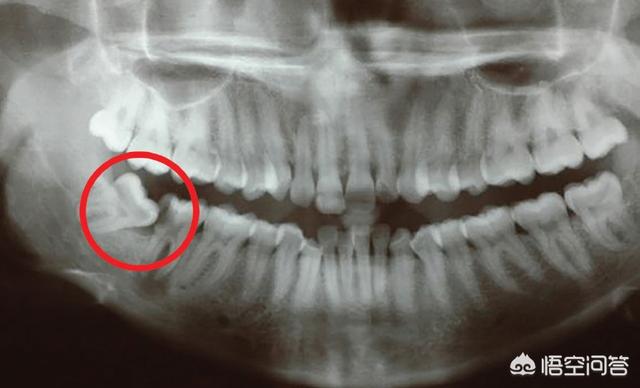

和所有猿类一样,所有人类祖先都有32颗牙齿包括三颗磨牙,现代人类可能会出现第三颗磨牙没有长出来的情况,据估计,全世界约有22%的人没有第三颗磨牙即智齿,所以当智齿在人类进化过程中成为不确定因素。智齿发育不全因人口而异,原住民塔斯马尼亚人的智齿发育几乎为零,而原住民墨西哥人的智齿发育几乎为100%。